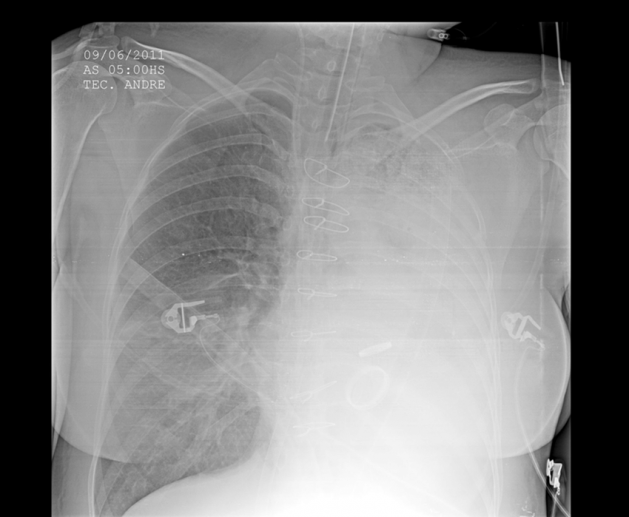

From FoamCAST: (https://foamcast.org/tag/hemoptysis)